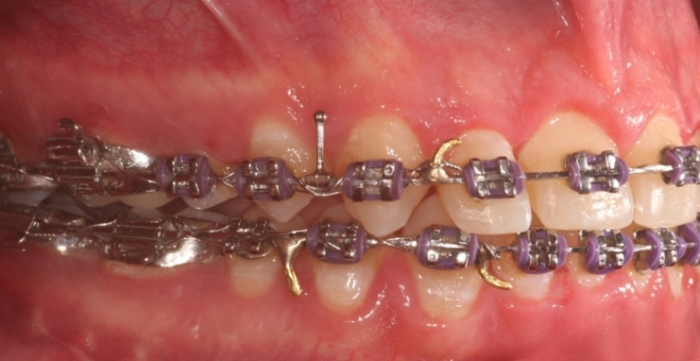

Mordida inicial